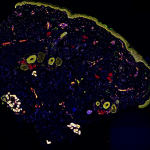

- This is a MADLI/MxIF image showing proteins & cells in the kidney made by HuBMAP researcher Allison Esselmen that won the “Image of the Poster Session” award at last week’s NIH-CZI Junior Investigators Meeting. Left side – MALDI-IMS of glomeruli, blue in background is the autofluorescence overlayed on top Right side – MxIF Magenta – podocytes, yellow – mesangial cells, teal – epithelial cells in proximal tubules, dark blue – vascular smooth muscle cells